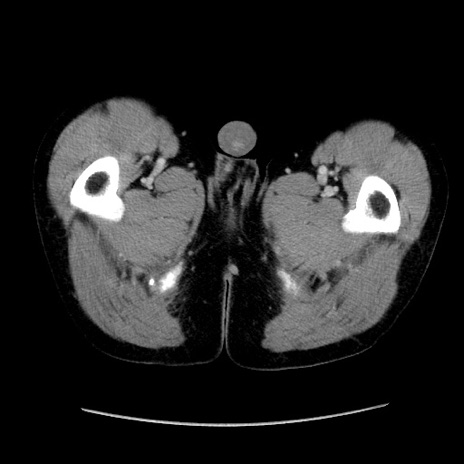

症例37(横断像)

【症例】40歳代 男性

【主訴】腹痛

【現病歴】4時間ほど前に電車に乗車中に臍部上より腹痛出現。徐々に増悪し起立困難となり、救急外来受診。生ものは数日食べていない。今朝お雑煮を食べた。

【身体所見】BT 36.8℃、BP 117/84mmHg、HR 91/min、SpO2 97%、苦悶様、腹部:臍上部広範囲圧痛あり、反跳痛±

【データ】WBC 8100、CRP 0.03